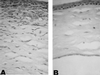

Onchocerciasis is a major cause of blindness. Although the World Health Organization has been successful in reducing onchocerciasis as a public health problem in parts of West Africa, there remain an estimated 17 million people infected with Onchocerca volvulus, the parasite that causes this disease. Ocular pathology can be manifested in any part of the eye, although disease manifestations are frequently characterized as either posterior or anterior eye disease. This review focuses on onchocerca-mediated keratitis that results from an inflammatory response in the anterior portion of the eye and summarizes what is currently known about human disease. This review also describes studies with experimental models that have been established to determine the immunological mechanisms underlying interstitial keratitis. The pathogenesis of keratitis is thought to be due to the host inflammatory response to degenerating parasites in the eye; therefore, the primary clinical symptoms of onchocercal keratitis (corneal opacification and neovascularization) are induced after injection of soluble O. volvulus antigens into the corneal stroma. Experimental approaches have demonstrated an essential role for sensitized T helper cells and shown that cytokines can regulate the severity of keratitis by controlling recruitment of inflammatory cells into the cornea. Chemokines are also important in inflammatory cell recruitment to the cornea, and their role in onchocerciasis is being examined. Further understanding of the molecular basis of the development of onchocercal keratitis may lead to novel approaches to immunologically based intervention.